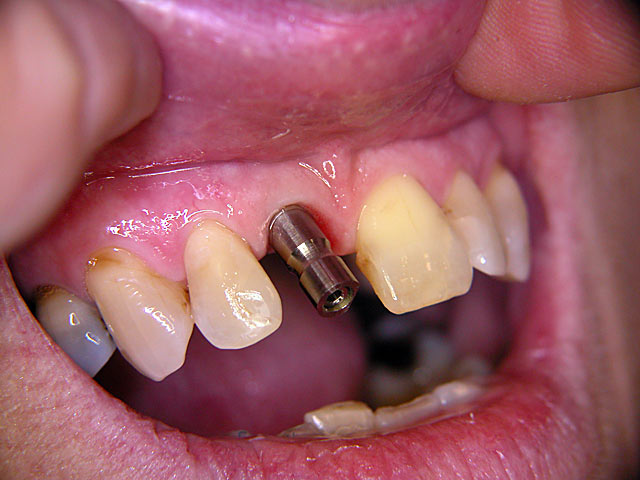

Frontzahn-Implantation: